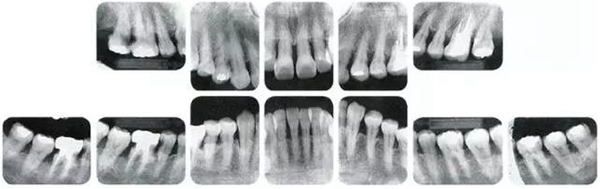

●參考病例② 25歲女性

25歲女性。菌斑控制狀態(tài)不好。齦溝除磨牙處外全在3mm以下,X光照片上左上、右下、左下的第一磨牙上有垂直性骨吸收。這個(gè)病例是參考病例①10年前的狀態(tài),是典型的侵襲性牙周炎局部型。

牙周病的發(fā)展因部位不同而發(fā)展程度不同的。10點(diǎn)后的狀態(tài)參考病例①和參考病例②的磨牙處的狀態(tài)相比較,思考下沒(méi)接受治療病情發(fā)展的特別性吧。

參考病例① 35歲女性

在左下第一磨牙在25歲時(shí)近中處可以看到垂直性的骨吸收,但35歲時(shí)吸收停止,原本沒(méi)有見(jiàn)到的遠(yuǎn)中處骨吸收的,現(xiàn)在卻吸收得很?chē)?yán)重。

在右下處,原本有大量骨吸收的第一磨牙處的吸收卻變緩慢,原本沒(méi)有吸收的第二前磨牙卻出現(xiàn)了吸收。出現(xiàn)吸收的左上第一磨牙的遠(yuǎn)中處,吸收得越來(lái)越多了。

把10年間的變化做成表格。牙周病的發(fā)展根據(jù)各個(gè)人會(huì)不同,即使通一個(gè)人,不同牙齒,不同牙面發(fā)展的狀態(tài)也不同。